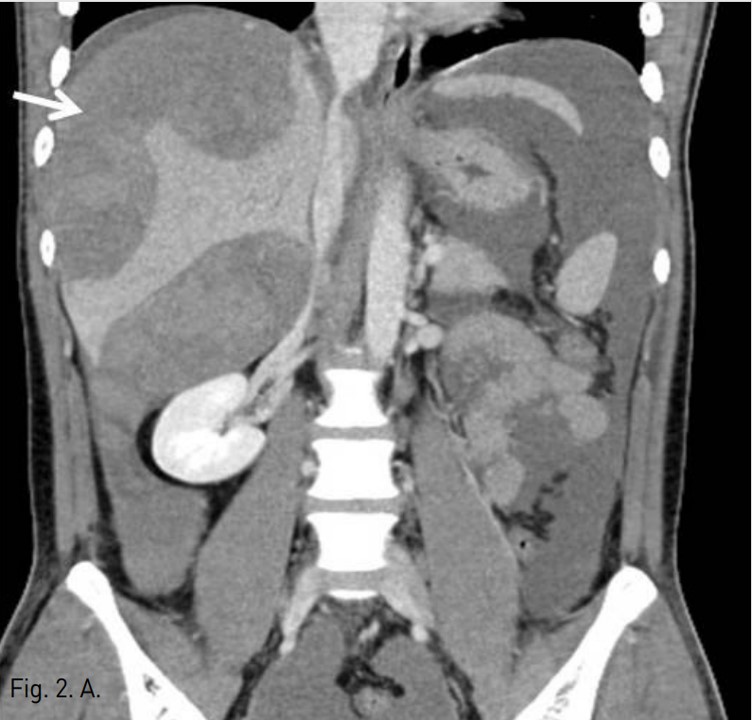

Fig. 2. A

Fig. 2A. The coronal CT image obtained 2 days after embolization shows a large diffuse expanding subcapsular hematoma (arrow).

5F RH catheter (Cook, Bloomington, USA)를 이용하여 바로 시행한 간동맥조영술에서 right posterior inferior hepatic branch에서 급성출혈이 관찰되었다(Fig. 1B). 2.9F coaxial microcatheter(Stride, ASAHI, Aichi, Japan) 로 출혈혈관부위를 초선택한 후 gelatin sponge(Cutanplast, Mascia Brunelli , Milan, Italy)을 이용하여 색전술을 시행하였다(Fig. 1C). 시술 다음날 혈색소 수치는 10.0g/dL로 증가하였다. 그러나 시술 2일 후 환자의 활력징후는 혈압 131/80mmHg, 맥박수 82/min로 안정적이었지만, 혈색소가 7.8g/dL로 급격히 감소하였고, 우상복부에 심한 통증을 호소하여 재출혈의 의심하에 복부 CT검사를 시행하였다. CT검사에서 간에 다량의 피막하 혈종이 관찰되었지만, 조영제의 혈관외 유출은 보이지 않았다(AAST grade Ⅲ)(Fig. 2A). 같은 날 시행한 간동맥 혈관조영술에서 기존 색전술을 시행한 동맥에서의 재관류는 없었지만, 새로 생긴 다른 부위의 피막하혈종 내로 광범위한 다발성 미세출혈이 관찰되었다(Fig. 2B). Microcatheter를 이용하여 각 출혈부위 근처의 segmental artery들을 선택한 후 gelatin sponge를 이용하여 광범위한 부위에 색전술을 시행하였고, 더 이상의 출혈은 관찰되지 않았다(Fig. 2C, D). 시술 후 환자의 혈색소는 정상화되었고 우상복부 통증은 점차 감소하였다. 이 후 뚜렷한 합병증 없이 입원 1달 후 퇴원하였다.